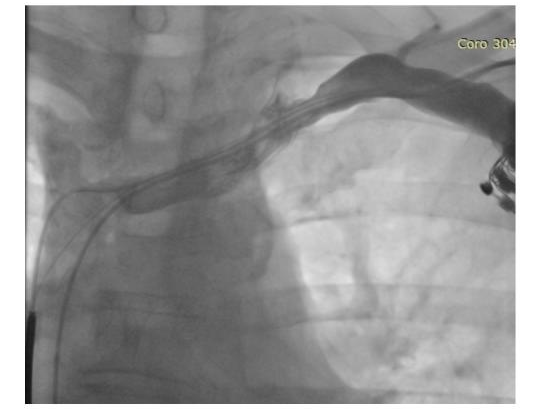

Previously the procedure the venography showed left subclavian vein patency with fibrosis along the lead (Figure 2).

Figure 2 Venography showed left subclavian vein patency with fibrosis along the lead.